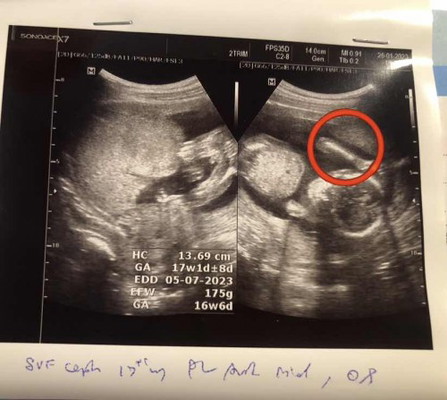

17 W 2 D ไปซาวด์มาคุณหมอบอกว่าได้ผู้ชายค่ะ

แม่ๆคิดว่าเพศไหนกันค่ะ มองเห็นชัดมั้ยค่ะ #ท้องแรกค่ะ ##ขอบคุณสำหรับคำตอบค่ะ

รูปที่วงมาหน้าจะเป็นขานะค่ะ แต่รูปแรกเป็นระหว่างขาน้อง หน้าจะผู้ชายค่ะจู๋มาเต็มเลย

รูปแรกค่ะ ผู้ชายค่ะแม่